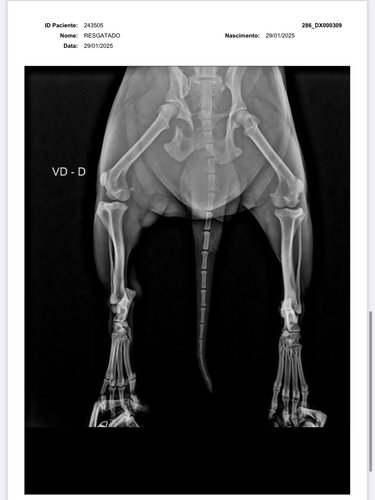

olá, eu sou a Samira, ajudo em uma ong de animais em Vilhena-RO e também resgato animais por conta própria. Encontrei esse pequeno cachorrinho abandonado a dias na chuva, sentindo tanta dor a ponto de não aceitar um sachê de comida. Levei ao veterinário e após buscar vários orçamentos, cheguei ao valor da vakinha, juntamente com a clínica Veterinária SOS animal, para a cirurgia do pequeno guerreiro. Não possuo condições de arcar com 100% da cirurgia, portanto, peço encarecidamente a ajuda de vocês para me ajudar e salvar a vida desse pequeno guerreiro. * Deixo abaixo o orçamento e os exames !